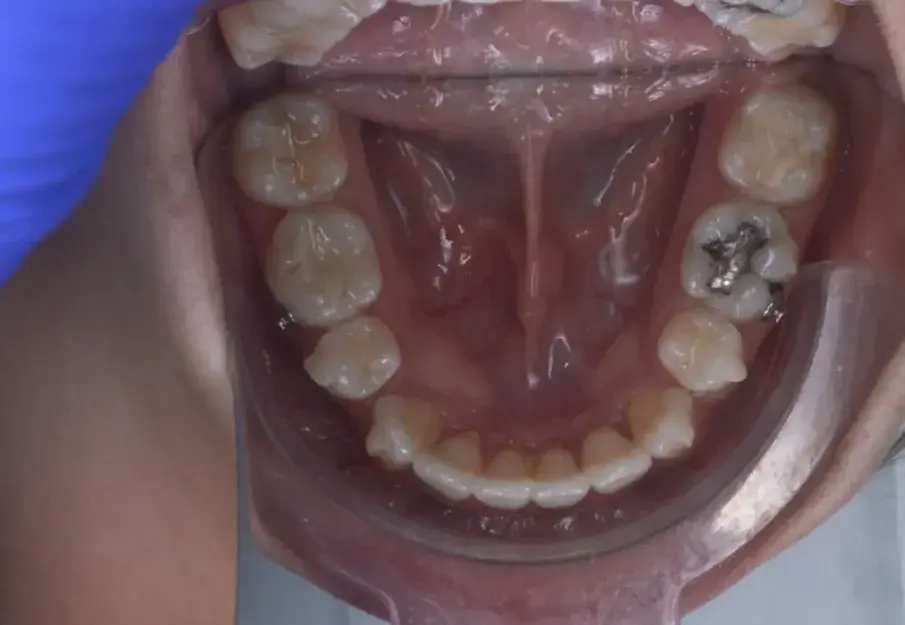

Фиг. 3а: Първоначални оклузални изображения.

Фиг. 3b: Първоначални оклузални изображения.

Фиг. 3c: Първоначални оклузални изображения.

35-годишна пациентка постъпва със струпване на зъби, болки в мускулите и ставите и главоболие след събуждане. При прегледа се установява I скелетен клас със струпване и бимаксиларна протрузия. Изследването на лицето показа конвексен профил с изпъкнали устни и квадратна форма на лицето, която се засилва при усмивка (фиг. 1-4). Тя съобщава за бруксизъм и се наблюдава двустранна хипертрофия на масетерите, но няма изменения в темпоромандибуларните стави.